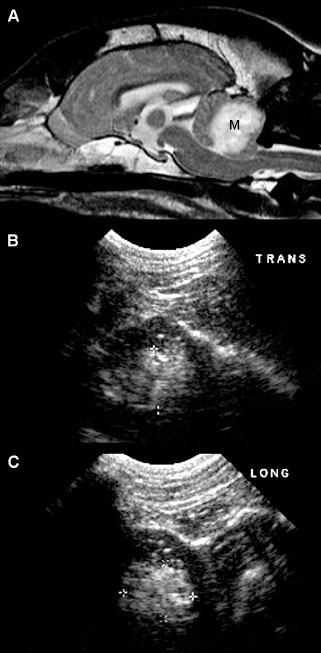

In young puppies, the bregmatic fontanel can be used as an acoustic window to the brain up to approximately 1 month of age (Hudson et al. 1991). In some individuals, particularly in toy-breed dogs, the bregmatic fontanels may persist into adult life. A kitten’s brain can be imaged through the fontanel up to about 5 months of age although accessibility decreases over time (Jäderlund et al. 2003). Unless the fontanel or defect is very large, the tip of the transducer must be held relatively stationary; the transducer can slide only a short distance. The brain is imaged by using a “windshield wiper” technique, with the tip of the probe acting as a pivot point to scan from rostral to caudal and back to obtain transverse images and from side to side to obtain longitudinal images. Because the probe is usually angled to view rostral and caudal structures, most images are made in oblique rather than perpendicular planes (Figure 1.1). Therefore, it should be remembered that, in rostral transverse images, ventral structures seen are actually located rostrally to dorsal structures in the image whereas, in the caudal transverse images, the ventral structures are located caudally to dorsal structures seen in the image.

In absence of a fontanel, a lower-frequency transducer (e.g., 5 MHz) can be used to penetrate the skull, enabling partial visualization of the brain. Penetration of the temporal bone can be used for this purpose in some small dogs in which the brain cannot be otherwise imaged (Figure 1.2A).

Visualization of caudal structures of the brain can be achieved by imaging at the foramen magnum (Figure 1.2B).

Figure 1.1. Normal brain in a dog and ultrasound beams resulting in planes 1 and 2. A: Sagittal magnetic resonance image of the brain of a normal golden retriever illustrating how the ultrasound beam (planes 1 and 2 represented by the arrows) passes through the brain when the beam is placed over the fontanel to obtain transverse sonograms. B: Plane 1 shows the ultrasound beam angled perpendicular to the long axis of the brain to image the rostral horns of the lateral ventricles. C: Plane 2 shows the ultrasound beam angled caudally to image the third ventricle and mesencephalon. D: Transverse magnetic resonance image of the brain of a normal dog showing the axis of an ultrasound beam over the fontanel to obtain midline and parasagittal sonograms (arrows).

Figure 1.2. A: Hydrocephalus. Transverse magnetic resonance image of a dog with hydrocephalus showing the axis of an ultrasound beam to obtain parasagittal images (arrows and corresponding planes 1 and 2). Plane 1 shows the beam angled laterally to obtain a parasagittal image. Plane 2 shows the axis of the beam to image the brain through the temporal bone. 3, third ventricle; CN, caudate nucleus; LLV, left lateral ventricle; and T, thalamus. B: Foramen magnum window. Sagittal magnetic resonance image of a cat showing the axis of the ultrasound beam (arrow) for imaging of the brain through the foramen magnum. The plane of the ultrasound beam passes through the cerebellum and midbrain. A sonogram of a normal cat made through the foramen magnum is on the bottom right. A histological image made in a similar plane is on the bottom left. M, midbrain; and V, vermis.